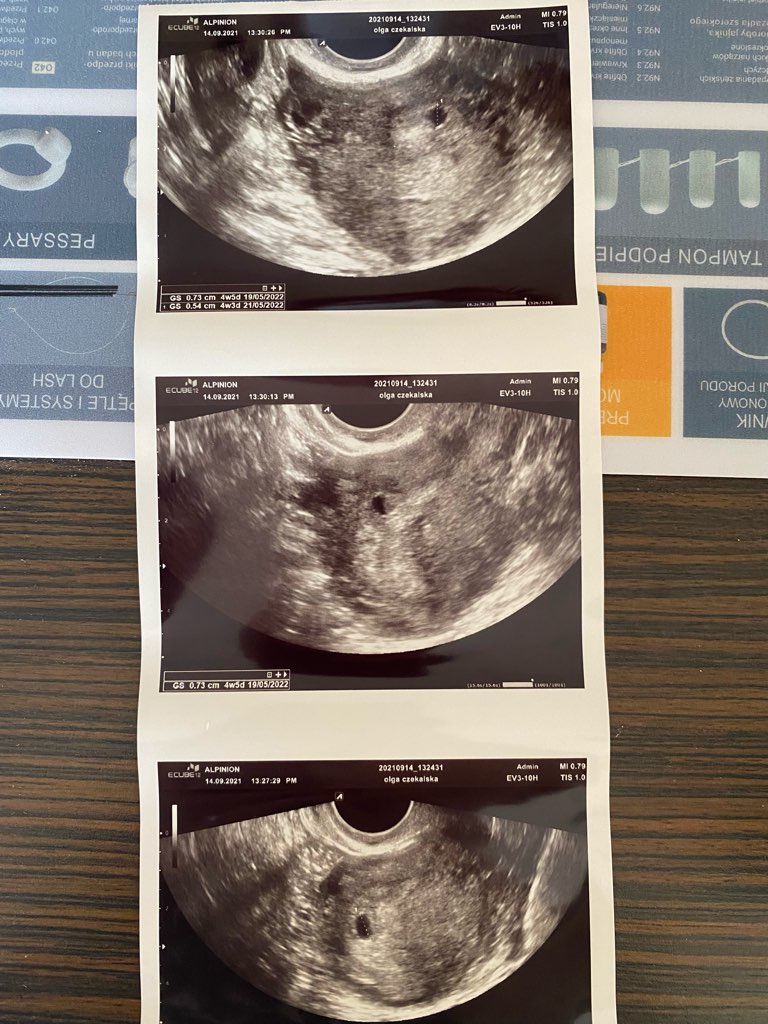

Dziewczyny, jestem po usg. Spodziewałam sie wszystkiego, ale nie tego, co usłyszałam. Nie ma pozamacicznej - co najwazniejsze. Ale za to sa prawdopodobnie TROJACZKI!!!!

Doszedł trzeci pęcherzyk. Prawdopodobnie przez nieregularny cykl mialam dwie owulacje w jednym miesiacu i doszło dwa razy do zapłodnienia. Beta tak wolno rośnie, bo dwa najmniejsze mogą polecieć. Jeden pęcherzyk super urósł przez ten tydzien, drugi tez jest troche większy niz ostatnio. Za tydzien znowu wizyta, mam juz nie powtarzać bety. Ciąża młodsza, największy pęcherzyk wychodzi na 4t5d. SZOK

Na środkowym zdjeciu dwa mniejsze pecherzyki, na ostatnim najwiekszy